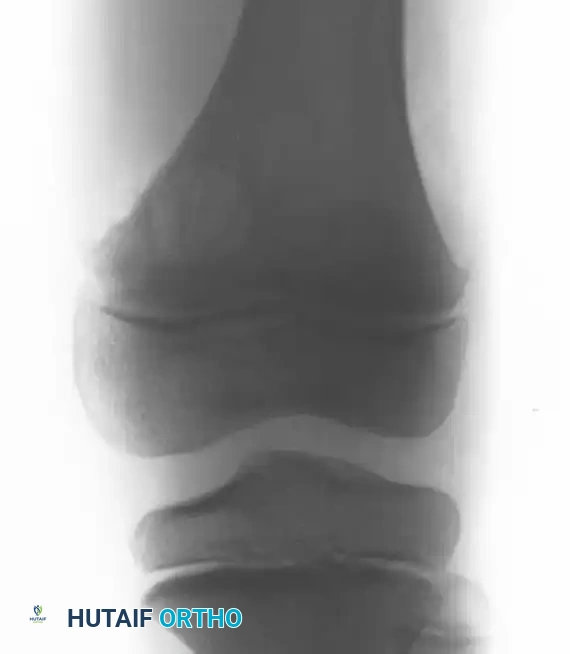

Fig. 20-9 A, B, and C: Eight-year-old boy with a cortical desmoid of the left femur. Anteroposterior radiograph (A) and corresponding Coronal (B) and Axial (C) MRI scans revealing cortical erosion with a sclerotic base.

The lesion is optimally visualized on an oblique radiograph with the lower extremity externally rotated 20 to 45 degrees. Advanced imaging (MRI) demonstrates focal cortical erosion with a thickened, sclerotic base and adjacent soft-tissue edema.

Clinical Pearl: The cortical desmoid is a classic "do not touch" lesion. Because its radiographic and MRI appearance can mimic early osteosarcoma or periosteal reactions, recognizing its exact posteromedial location is critical. Biopsy is strictly contraindicated, as the reactive histological features can be misinterpreted as a malignancy. No treatment is necessary.